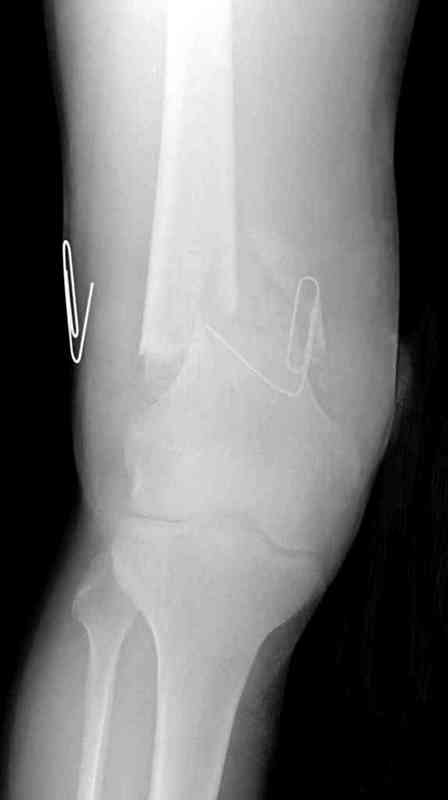

Пострадавшему 23, пистолетная огнестрельная не кроветочащая рана, меньше одного см диаметром, входное отверстие расположено латерально, и выход передне-медиально, и еще имеется второе пулевое ранение правой navicular bone с этой стороны.

Несмотря на сниженный до 0.9 BI-ankle-brachial-index (обязательное, недорогое исследование при подозрении на повреждение сосудов, рассчитанный по разнице давления в нижней и верхней конечности), последующее КТ ангиограмма не подтвердила повреждения артериальных сосудов.

Доступ был латеральный, при вскрытии с задней

поверхности бедра обнаружили кровотечение. Поднятием давления на заранее установленном турникете на конечности проконтролировали кровотечение.

В данном случае мы не ставили осуществление гемостаза приоритетным, после 30 минут больной оставлен вызванному сосудистому хирургу со стабильной фиксацией бедра. Несмотря на выбранный передне-медиальный доступ, хирург произвел восстановление сосудистого повреждения.

При близости сосудов к многооскольчатому повреждению костей, сперва необходимо удостовериться в наличии повреждения сосудов без применения турникета.